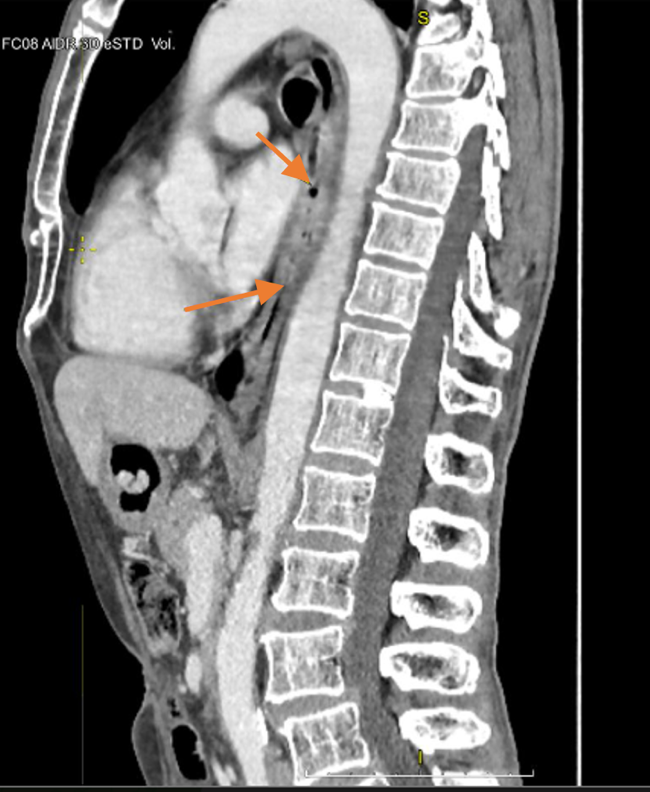

Материал и методы. Представлено 3 клинических случая одновременного развития плоскоклеточного рака пищевода и аденокарциномы желудка у пациентов, получавших лечение в ГУЗ «Областной клинический онкологический диспансер», г. Ульяновск, и ГАУЗ СО «Свердловский областной онкологический диспансер», г. Екатеринбург. Пациентам проведены хирургическое вмешательство, химиотерапия и лучевая терапия.

Результаты. Первично-множественный синхронный плоскоклеточный рак пищевода и аденокарцинома желудка представляют собой сложную клиническую задачу, требующую вмешательства мультидисциплинарной команды специалистов. Химиолучевая терапия с использованием схемы FOLFOX продемонстрировала хорошую переносимость и позволила достичь удовлетворительного клинического ответа со стороны опухолей обеих локализаций.